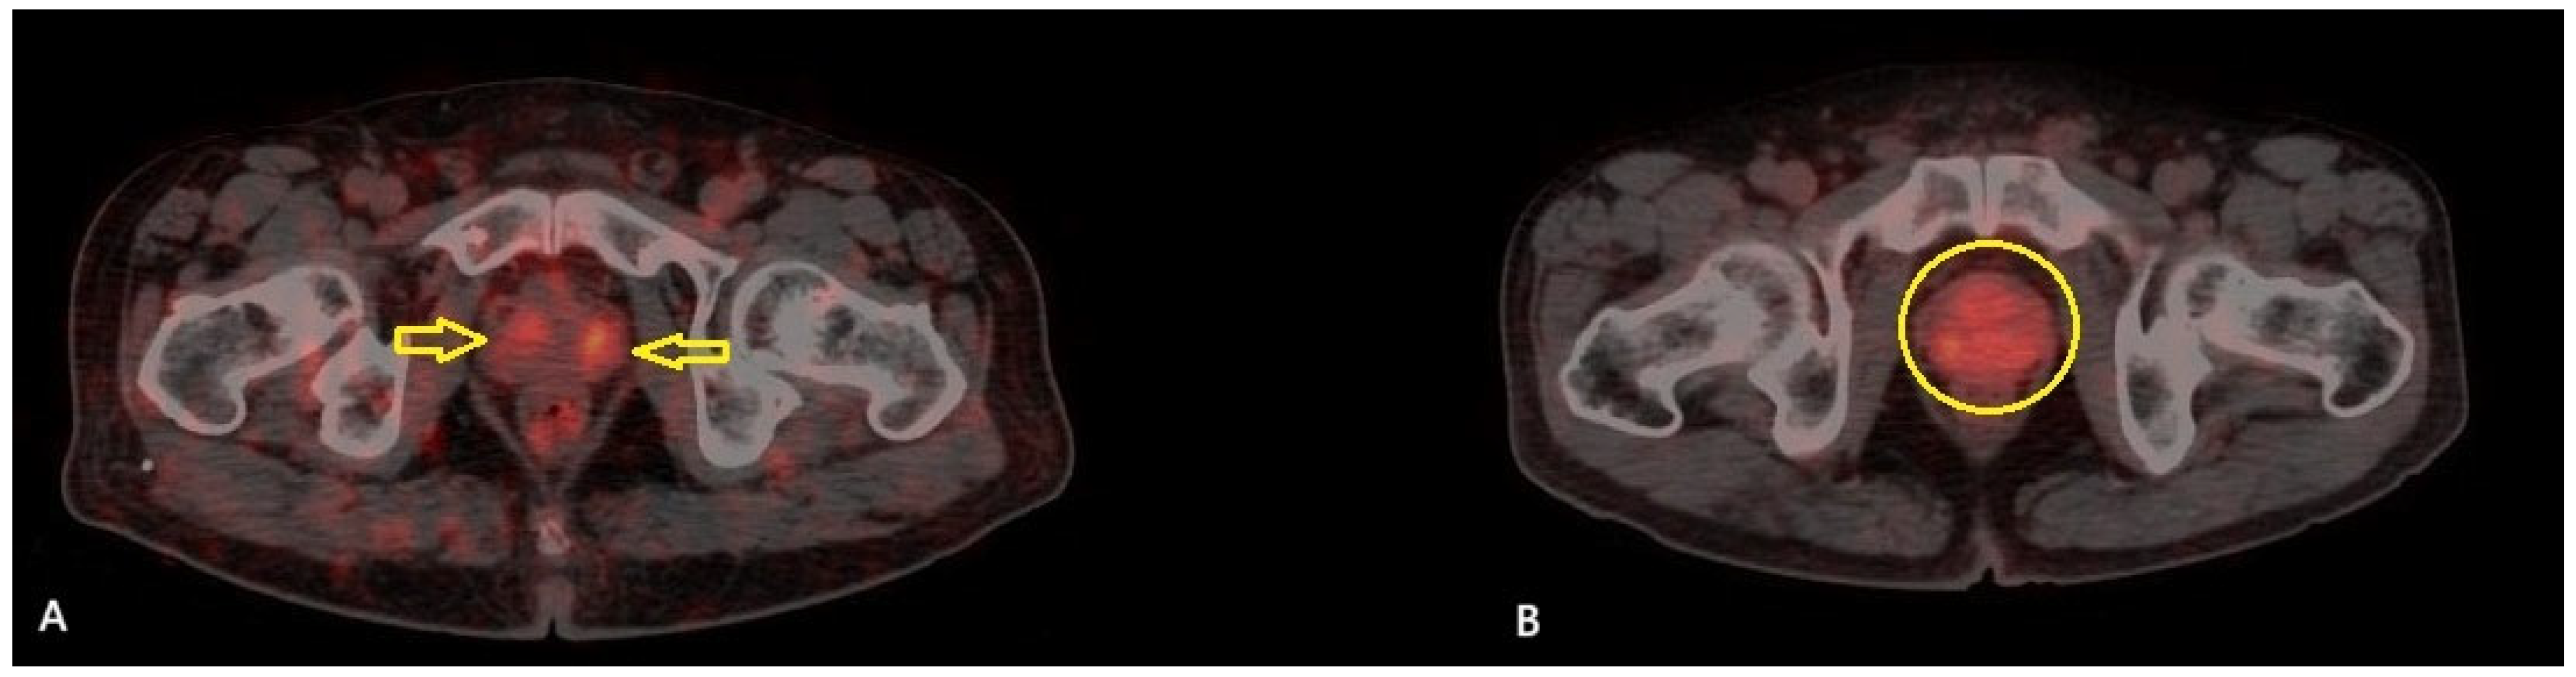

A total of 51 patients were included in the study. The mean age of the patients was 71.2 ± 7.4 years (range: 54–89), and the median serum PSA level was 20.3 ng/mL (IQR: 8.45–53.95). Among the patients, TUR-P was performed in 32 (62.7%) patients, while 19 (37.3%) underwent total prostatectomy. According to the pathology results, 11 patients (21.6%) were classified as GG 2, 4 patients (7.8%) as GG 3, 1 patient (2%) as GG 4, and 35 patients (68.6%) as GG 5. The patients were classified according to the D’Amico risk stratification system: 39 patients (76.5%) were classified as high risk, while 12 (23.5%) were in the intermediate-risk group. Based on the PRIMARY score analysis, 17 patients (33.3%) were categorized as PRIMARY Score 2, 6 patients (11.8%) as PRIMARY Score 4, and 28 patients (54.9%) as PRIMARY Score 5. None of the patients in this cohort was classified as PRIMARY Score 1 or 3. A summary of the clinical and histopathological characteristics of the study cohort is presented in Table 2. Among the 17 patients categorized as PRIMARY Score 2, 11 (64.7%) were classified as ISUP GG ≥ 3, and 10 (58.8%) were in the high-risk category according to the D’Amico classification (Figure 1).

Figure 1. (A): Axial [68Ga]Ga-PSMA PET/CT fusion image of a 70-year-old male with high-risk prostate cancer (D’Amico classification), ISUP Grade Group 5 (Gleason 5 + 4), and a PSA level of 5.9 ng/mL, demonstrating increased symmetrical PSMA uptake in the transition zone (yellow arrows) (SUVmax: 5.3). (B): Axial [68Ga]Ga-PSMA PET/CT fusion image of a 65-year-old male with high-risk prostate cancer (D’Amico classification), ISUP Grade Group 5 (Gleason 4 + 5), and a PSA level of 26.7 ng/mL, demonstrating diffuse PSMA uptake in the transition zone (yellow circle) (SUVmax: 4.6). Both lesions received a PRIMARY Score of 2 from all three readers.